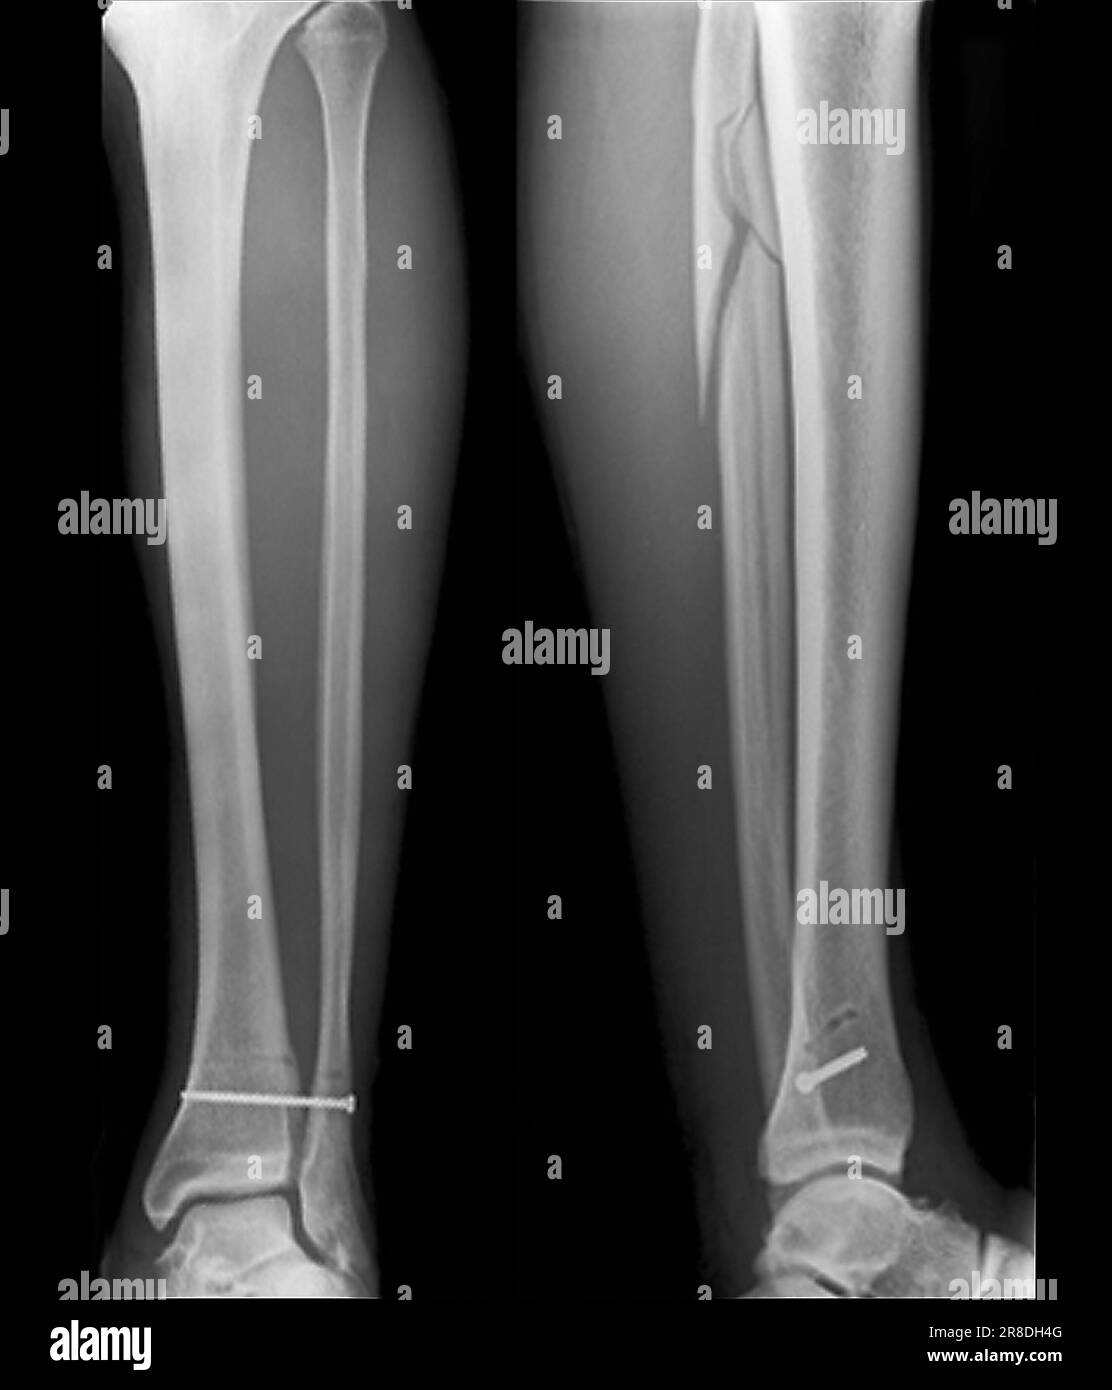

Coloured Xrays of the pinned ankle of a 32 year old male patient. A Calf In Bone Fracture A broken leg (leg fracture) is a break or crack in one of the bones in your leg. Fibula fractures occur around the ankle, knee, and middle of the leg. There are different types of fractures, which can also affect treatment and recovery. If you have a displaced fracture, the care. Common causes include falls, motor vehicle accidents. A broken. Calf In Bone Fracture.

Xrays of the pinned ankle of a 32 year old male patient. A screw is Calf In Bone Fracture What is a broken leg? There are three bones in your leg, including. Healthcare providers also call broken legs fractured legs. Common causes include falls, motor vehicle accidents. Here, health care providers typically evaluate the injury and immobilize the leg with a splint. A broken leg is a bone fracture (broken bone) in your leg. A broken leg (leg fracture). Calf In Bone Fracture.

Xray of the pinned ankle of a 32 year old male patient. A screw is Calf In Bone Fracture What is a broken leg? The proximal tibia is the upper portion of the bone where it widens to help form the knee. Healthcare providers also call broken legs fractured legs. The fibula, or calf bone, is a small bone located on the outside of the leg. A broken leg (leg fracture) is a break or crack in one of. Calf In Bone Fracture.